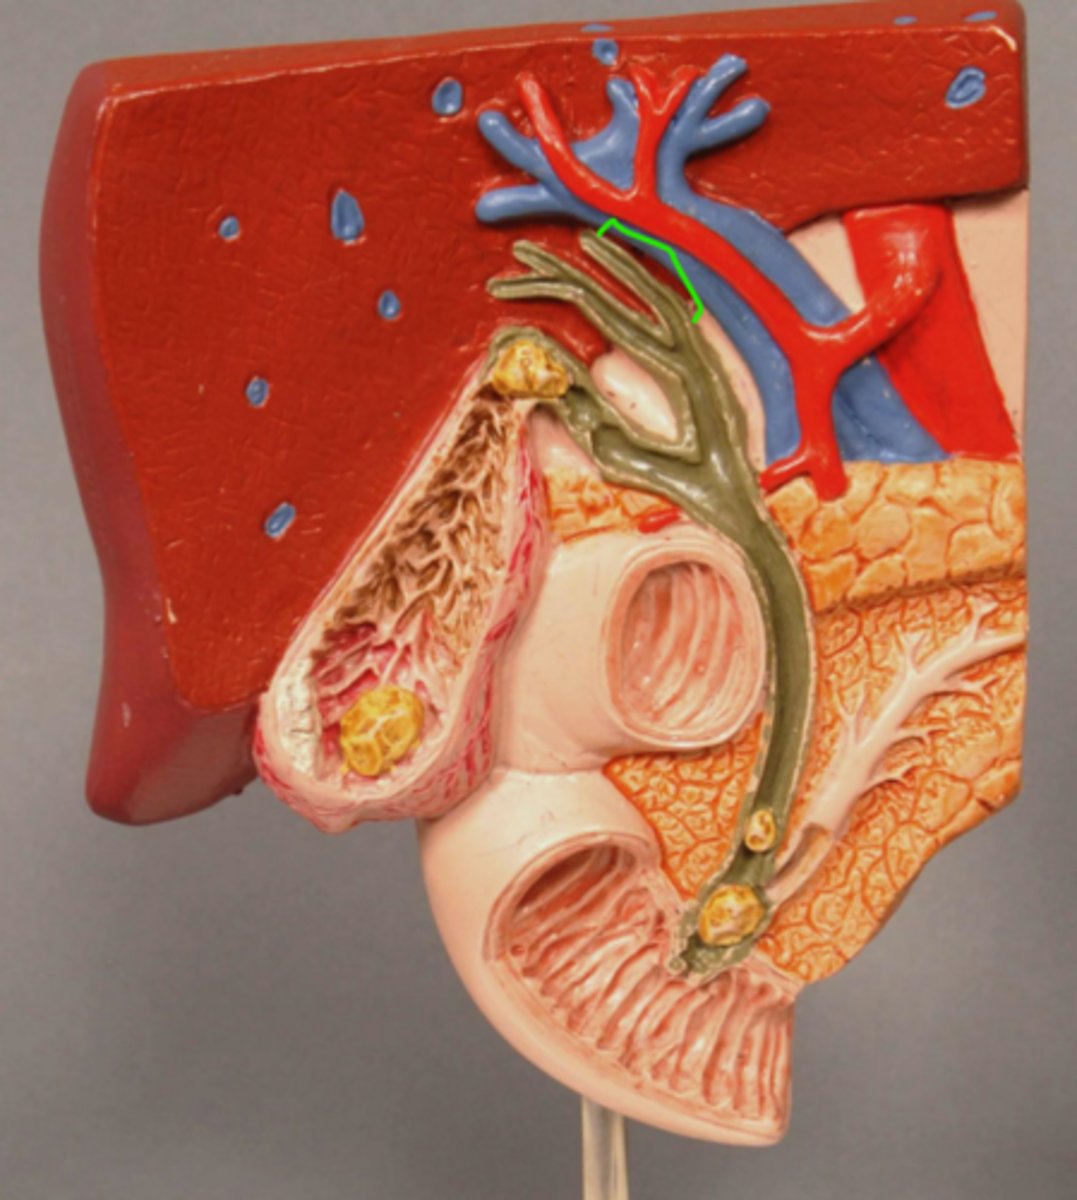

Gallstone Model

Left Hepatic Duct

Right Hepatic Duct

Common Hepatic Duct